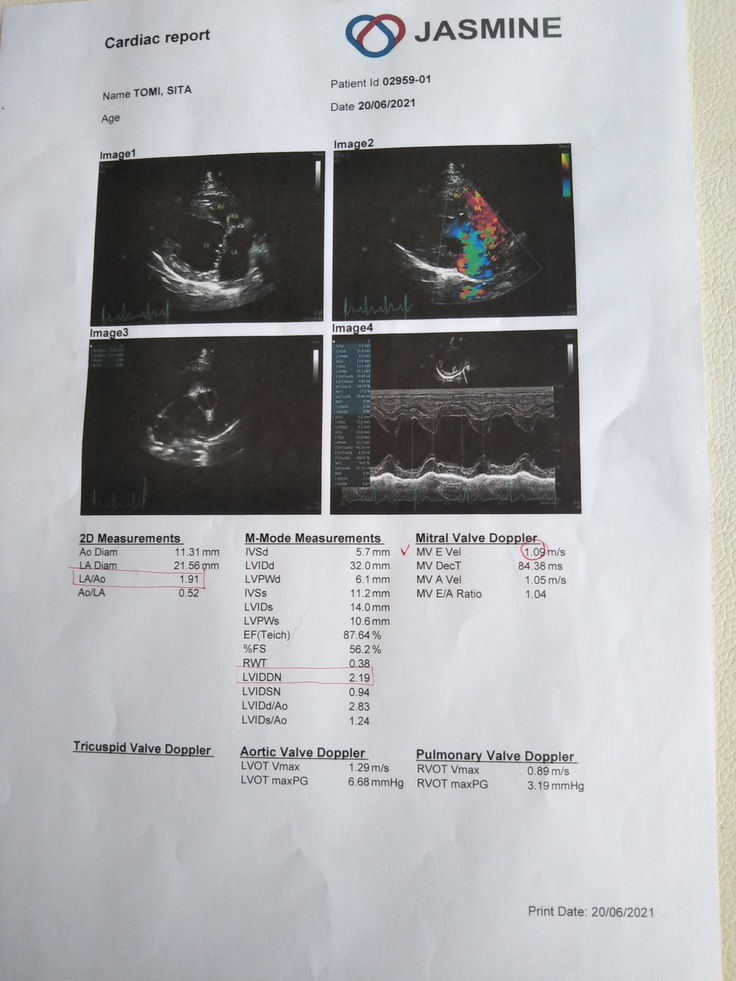

レントゲンとエコーの結果、僧帽弁閉鎖不全症ステージB1と診断されました。

診断名・・・僧帽弁閉鎖不全症、三突弁閉鎖不全症↑

現在お世話になっているいるJASMINE 動物総合医療センターで8月に手術の予定を年内にとお話を頂きました。肺水腫になって苦しむ前に手術をした方がよいとの事でした。

シータは現在ステージB2です。

入院費、手術費用で190万、術後の回復によっては入院費用は大きく変わるそうです。

心臓はやはりギリギリの状態まで来ていていつ心不全を起こしてもおかしくない状態まで進行していました。